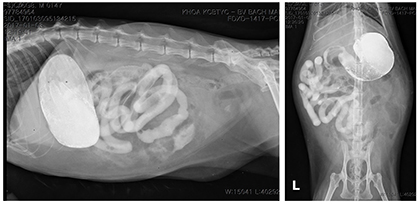

재 내원 시에 방사선 상에서 복강 전체적으로 serosal detail이 감소되어 있으며, free air도 확인됐다. 복강 초음파 영상에서도 복수의 존재를 확인했다. 추가적인 진단검사를 위해 peritoneocentesis를 실시하여 복수 샘플을 확보하고, 검사 의뢰했다.

복강 내 천공이 의심되어 추가로 조영검사를 진행했고, 조영제 투여 후 3시간 뒤 촬영에서 소장내의 조영제가 복강 내로 누출되는 것을 확인하여 천공 부위가 공장 내에 있는 것을 확인했다[그림 1].